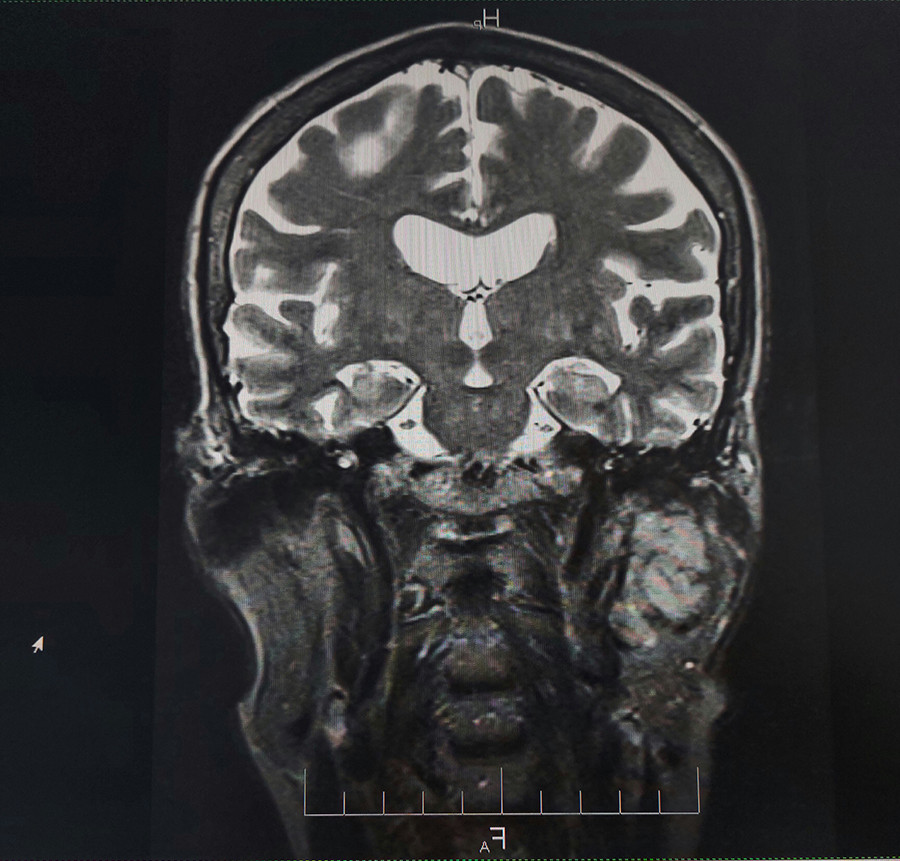

Նախքան «Նաիրի» ԲԿ դիմելը պացիենտի մոտ ախտորոշվել է հարականջային թքագեղձի ադենոմա։ «Նաիրի» բժշկական կենտրոնում կատարվել է թքագեղձի մագնիսա-ռեզոնանսային տոմոգրաֆիա, և պարզվել, որ ավելի քան 5 տարի գոյություն ունեցող թքագեղձի ադենոմայի ներսում առկա է մոտավորապես 1 սմ պինդ գոյացություն։ Իրականացվել է հայտնաբերված պինդ գոյացության պունկցիոն բիոպսիա և, արդյունքում, ախտորոշվել է ուռուցք` թքագեղձի ադենոկարցինոմա: Սա այն դասական դեպքերից է, թե ինչպես կարող է բարորակ գոյացությունը, տարիներ շարունակ անտեսելու, չբուժելու արդյունքում վերաճել չարորակ ուռուցքի։

Քանի որ գոյացությունը մեծ էր և շատ մոտ էր գտնվում դիմային նյարդին (դիմային նյարդը նյարդավորում է դեմքի միմիկայի բոլոր մկանները), կատարվեց ամբողջական հեռացում: Մանրադիտակի կիրառման պայմաններում դիմային նյարդն ամբողջապես պահպանվեց։ Երկու-երեք ամիսների ընթացքում դեմքի միմիկայի բոլոր մկանները վերականգնվեցին՝ թե՛ ֆունկցիոնալ, թե՛ էսթետիկ առումով, ինչը թույլ տվեց մեր պացիենտին շարունակել իր մասնագիտական գործունեությունը։